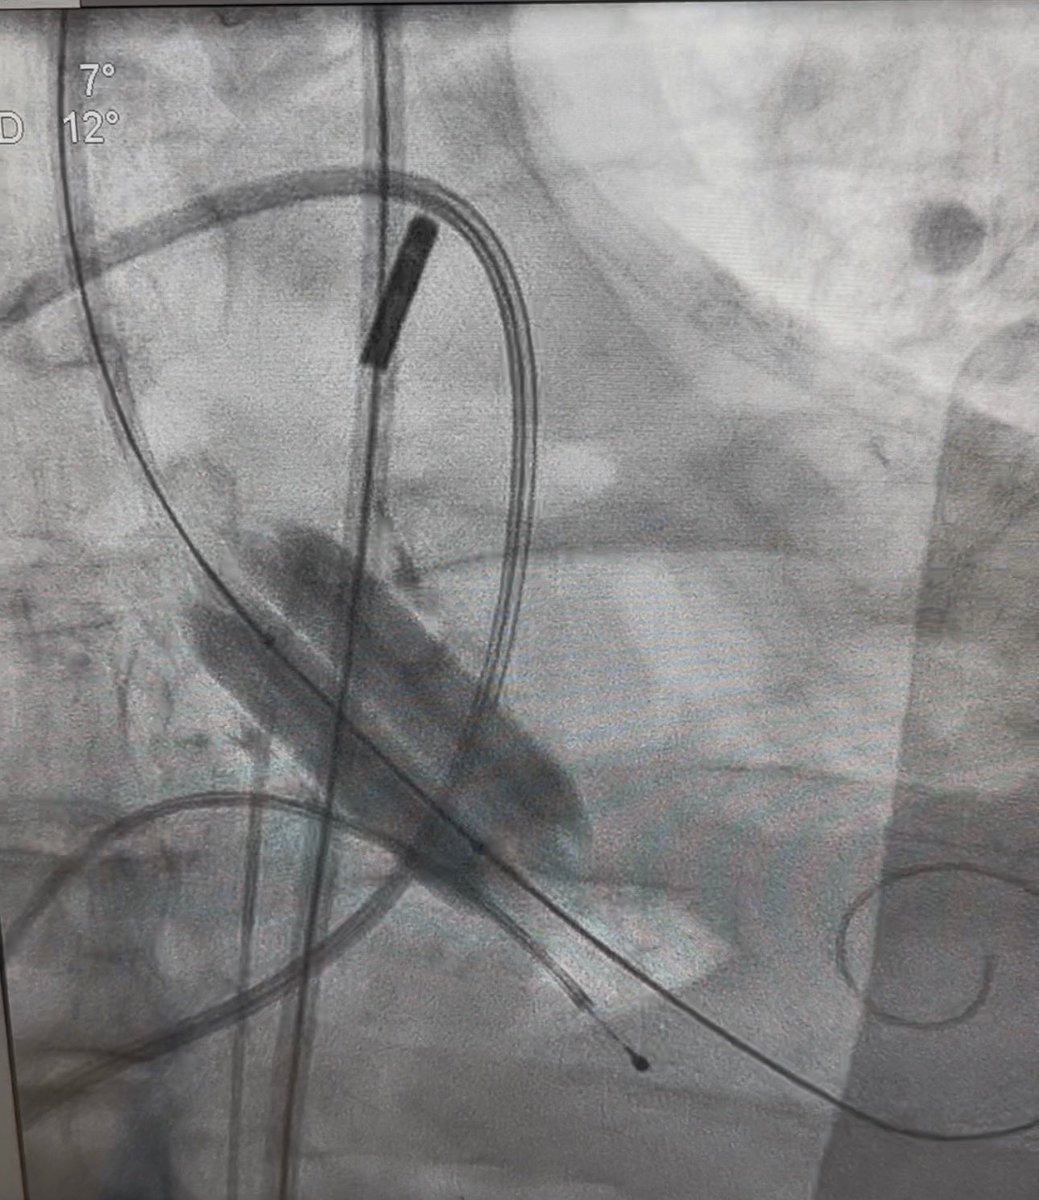

Excited to share our paper, now out in @JACCJournals! Important work led by @MAlvarezVillela:

🔥 Fever in AMI-CS is common and is associated with greater illness severity but seems to be noninfectious in most cases

#CardiogenicShock 🫀